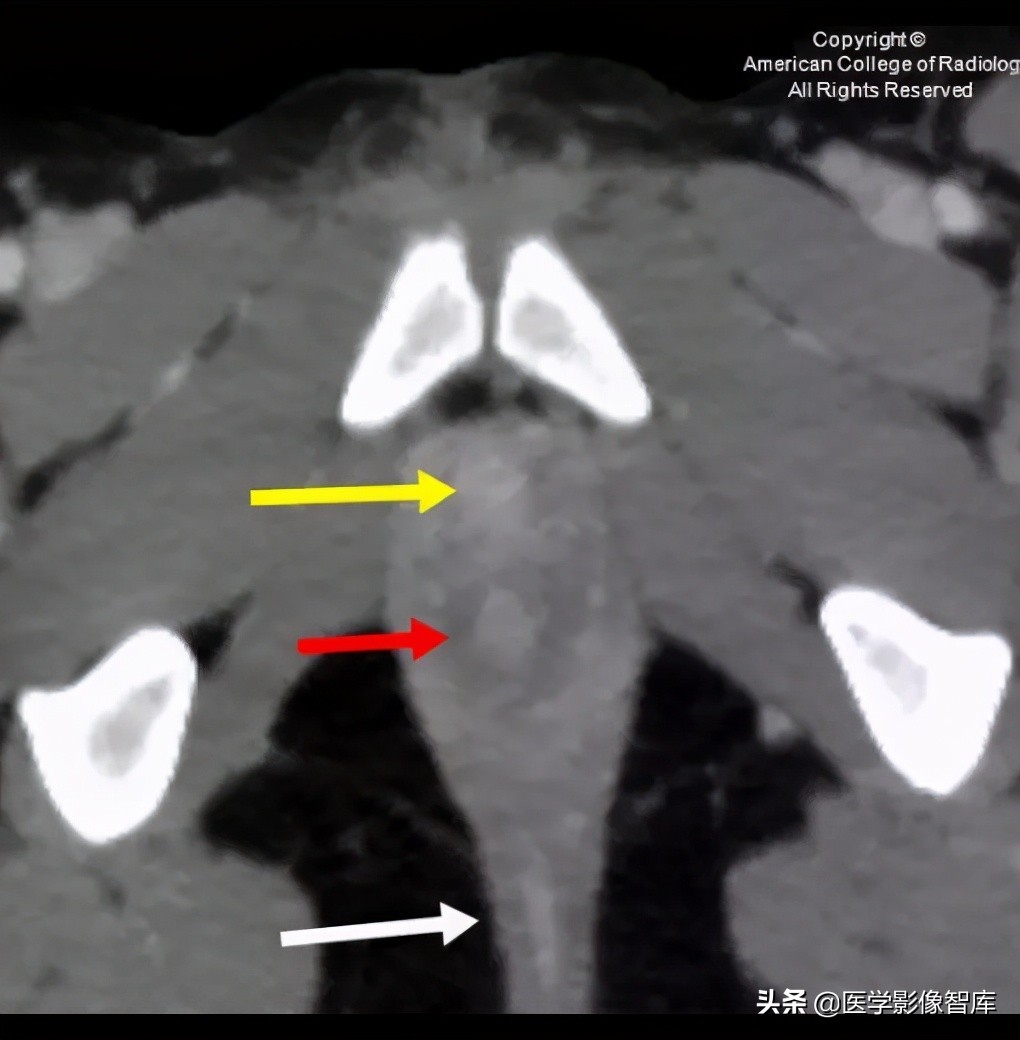

图 9. 轴位 CT 显示尿道(黄色箭头),阴道发育不全(红色箭头),直肠(白色箭头)